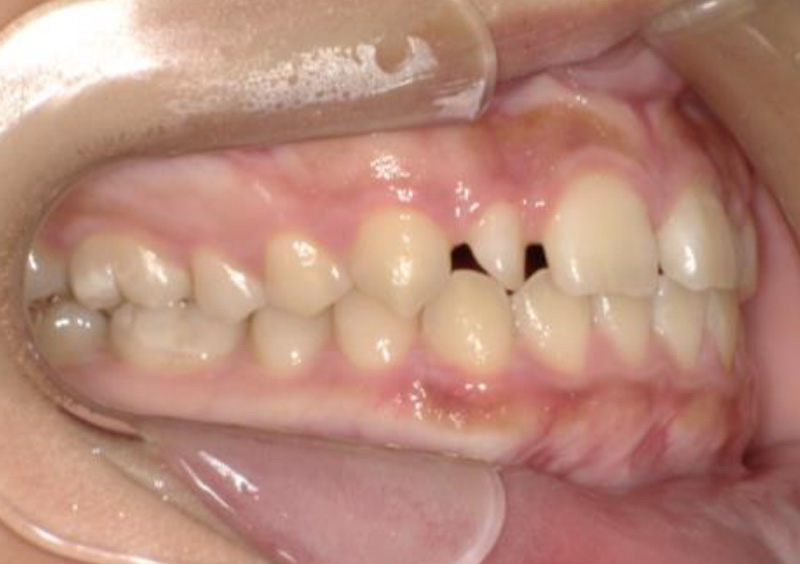

大人の矯正治療 歯に隙間がある(空隙歯列) 2025.10.24 【マルチブラケット矯正】隙間が気になる 治療前 治療後 担当医 一瀬 悠依華 先生 主訴 隙間が気になる。 期間 2年半 費用 65万円 治療内容 マルチブラケット装置 治療に伴うリスク 歯根吸収、歯肉退縮 関連症例